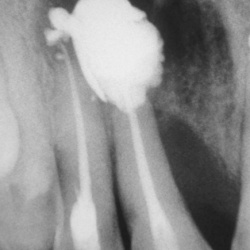

Какие мнения будут по снимкам?Первый пациент.Второй пациент.

Зубы.Первый пациент.Второй пациент.Третий пациент.